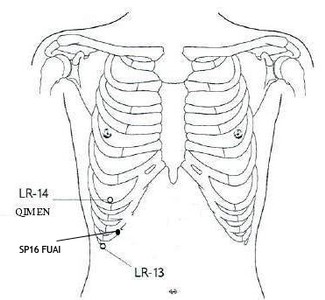

LR-14 qimen, porta clinica

SP-16 fuai, dispiacere dell'addome

Qimen si trova sula verticale del capezzolo, nel VI spazio intercostale, più sotto è c'è SP-16 fuai. Punto Mu del Fegato e d'incontro dei canali della Milza e del Fegato. La zona è importante per i trattamenti che richiedono di migliorre il movimento del Qi di Fegato e di regolare lo Stomaco-Milza. Anche Qimen ha molteplici utilizzi connessi al rapporto Fegato e Milza; si usa per esempio nei casi di dolori all'ipocondrio, nausea, vomito, sonno agitato e malattie febbrili da Freddo.